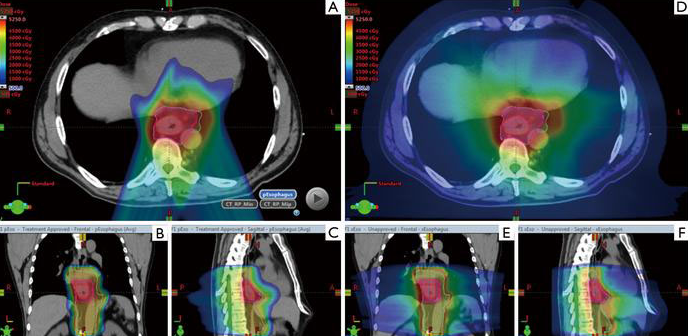

▲質(zhì)子治療食管癌,